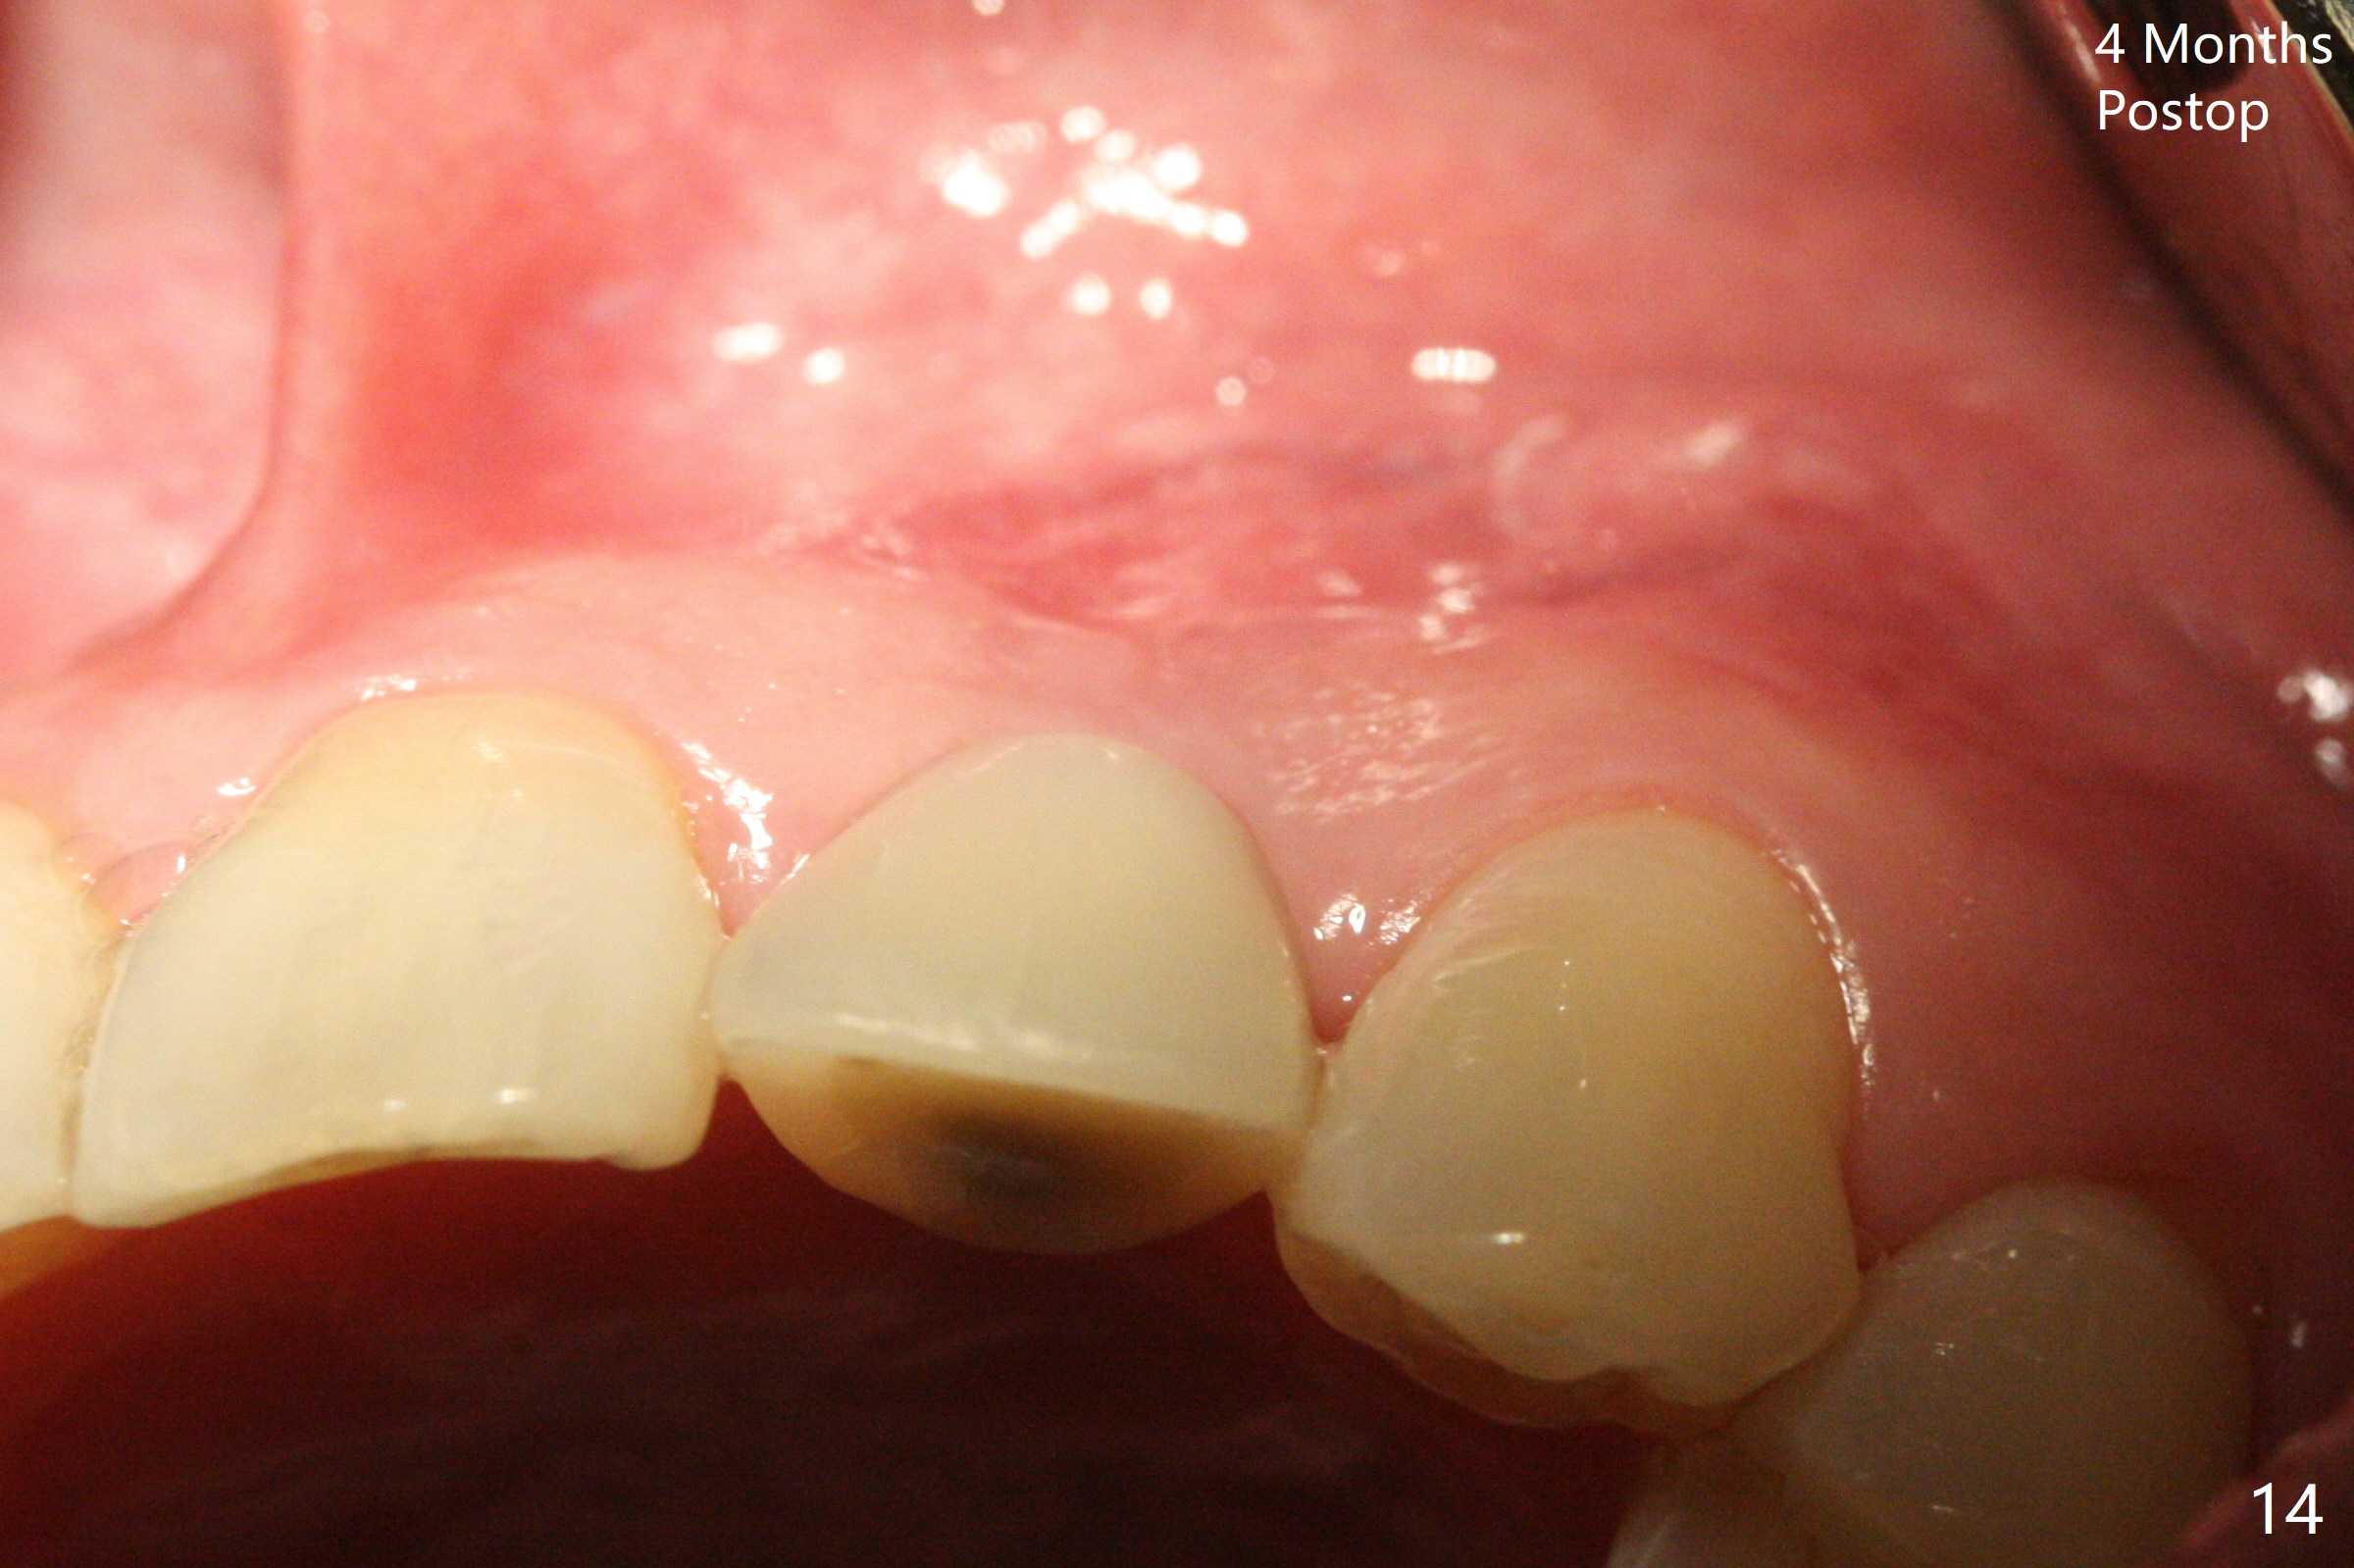

病人回来带来瘘道(图一),不过不会增加难度,病牙去除,它便自动消失。尽管颊侧骨壁完全失去,颊侧牙龈仍丰满(图二),为什么呢?第一,因为粗大牙根存在,第二两旁牙齿,牙槽骨撑着帐篷(侧切牙颊侧牙龈),第三,牙冠。为了防止术后牙龈塌陷,尽量不切开,即刻放置植体(牙根);由于前牙缘故,这次植体不能很大,所以植骨必须过度(over grafting),最后即刻制作临时牙冠,撑住牙龈。这就是所谓每个人进入角色。这个牙根有一种先天性畸形:dens in dent (图三(腭侧观):箭头)。尽管腭侧牙根畸形,腭侧骨壁吸收临床上并不严重,所以钻洞仍偏腭侧。当预定最后钻头还在钻洞时,填入大量粘性骨块(图四:*),细长植体还没有完全卡入鼻底(图五),最后好像可以(图六,七)。植体,骨粉入位(图八),最后临时牙冠出场(图九)。尽管植体小,术后一周临时牙冠仍然可以维持牙龈原有形状(emergency profile,图十:箭头(*:树脂强化牙冠固定))。图十一以不同角度显示瘘道缩小。术后三周取出有些松动的临时牙冠,骨粉虽然还没有被肉芽组织整合,但是显得正常,周围牙龈健康(图十二)。术后4个月牙龈形态正常(图十三),没有触痛;颊侧骨板轻度凹陷(图十四);骨粉仍在原位(图十五)。术后7个月骨粉仍在原位(图十五,十六,但是冠部密度减低(可能骨粉流失,需要牙周或者树脂敷料保护)),没有螺纹暴露。但是牙冠边缘暴露,说明牙龈收缩(图十七,与图十三对比),颊侧骨板仍塌陷(图十八)。插入龈线取得多个目的:修整基台边缘,取模,颊侧牙龈推向颊侧,有利于即将衬里牙冠龈缘进入龈下(图十九)。取模后牙冠边缘(图二十:<)衬里,然后修整,变窄,以便插入龈下,促进颊侧牙龈下降(图二十一,二十二)。术后8个月牙冠粘固前牙龈健康(图二十七,八),牙冠(图二十九)固位后,病人满意(图三十),咬合调整(图三十一),注意腭侧粘固粉流出通道(<)。